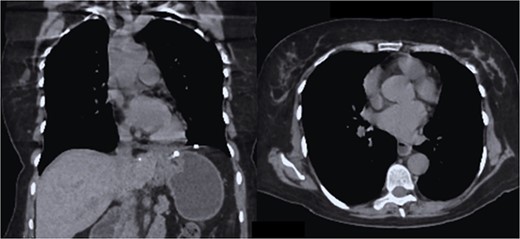

The case is reported of a 52-year-old woman, without significant illnesses, who presented with non-specific chest pain for 1 year, 6 months later with intermittent episodes of dyspnea with great and medium exertion, dysphagia, and heartburn. During the examination, hypoventilated lung fields at the bases, peristaltic sounds, and tympanism on percussion were heard. The thoracoabdominal tomography with contrast shows a diaphragmatic hernia containing the stomach, portions of the duodenum, pancreas, small intestine, and colon (Fig. 1), with a sac measuring up to 20 cm (Fig. 2).

CT coronal section, showing the presence of the stomach, duodenum, small intestine, colon, and pancreas.

CT in axial section, hernia sac measuring ~21 × 15 × 7 cm is observed.